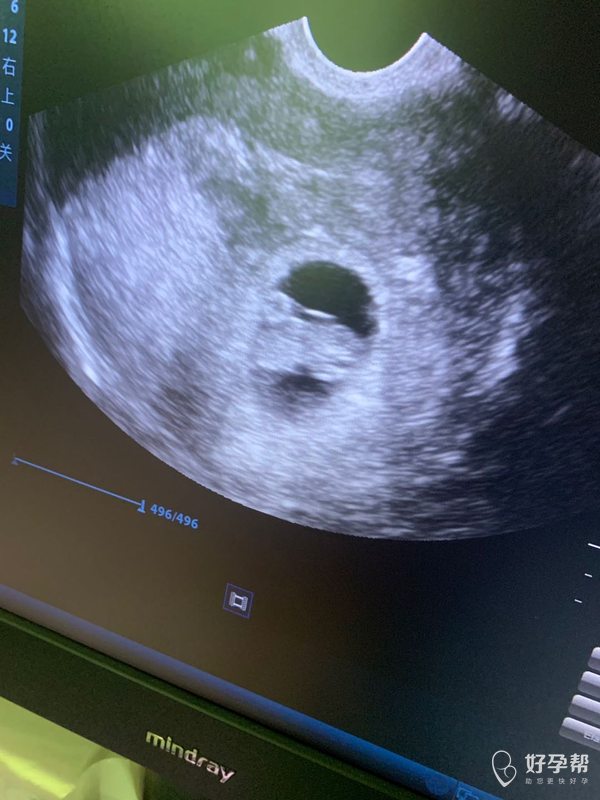

这张照片正常的吗图品中有没有宫腔积液或者盆腔

这张图片没有看到明显宫腔积液和盆腔积液,看到了卵黄囊和一小胚芽,胎心要动态看,图片不是太清楚看起来难一些,恭喜宫内怀孕了,有7周左右?